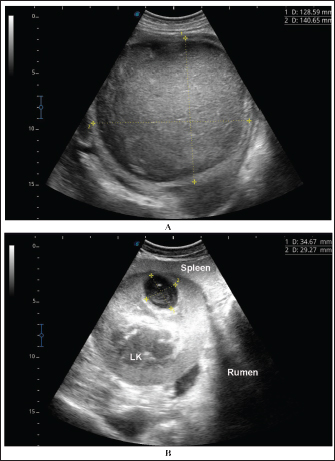

Fig. 8. Ultrasonographic findings in camel number 11 with right and left kidneys. Image A shows 2 abscesses within the right kidney (RK) and measuring 7.6 × 6.9 cm and 9.3 × 8.1 cm with isoechoic contents. Image B shows a relatively large abscess in the left kidney, and measuring 11.9 × 15.0 cm and with isoechoic contents.

Ultrasonographic findings in camel number 9 with right kidney abscesses are shown in Figure 7, where the lesion appeared compressing the parenchyma of the right kidney. Its contents are hyperechoic, and its capsule is thick. Figure 8 shows sonographic findings in camel number 11 with abscessation of the right and left kidneys. Abscesses measured 7.6 × 6.9 cm and 9.3 × 8.1 cm with isoechoic contents. A third abscess in the same camel was found within the left kidney. It was relatively large and was isoechoic. Ultrasonographic findings in camels 15 and 16 with abscesses of the left kidney are shown in Figure 9. A large abscess was found in camel number 15 with isoechoic contents and a thick capsule, while a small abscess was imaged in the left kidney of animal number 16 with heterogeneous contents. Figure 10 shows the ultrasonographic findings in camel number 17 with abscessation of the left kidney. A large abscess was found compressing the parenchyma of the left kidney with isoechoic contents. The urinary bladder in the same camel contained echogenic deposits that appeared to be highly echogenic.